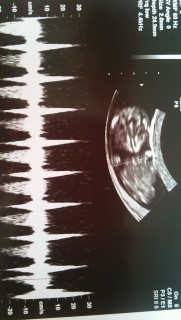

手をウネウネ動かして楽しそう♪ 心拍も確認できました!